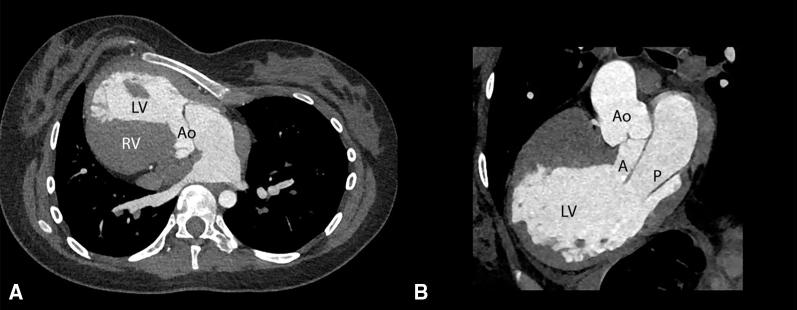

Robotic mitral valve repair in a patient with cardiac dextroversion.

JTCVS Tech. 2021 Oct 23;11:12-16. doi: 10.1016/j.xjtc.2021.10.031. eCollection 2022 Feb.